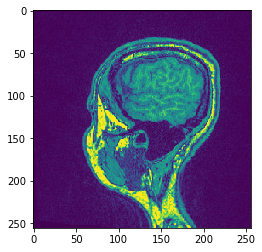

Proyección#

pyclesperanto ofrece proyecciones de mínimo/media/máximo y suma en x, y y z.

# Proyección Z Máxima

projection = cle.maximum_z_projection(input_image)

# mostrar resultado

cle.imshow(projection)

Si pasa una pila de imágenes a cle.imshow, realizará la proyección de intensidad máxima a lo largo de Z por usted:

cle.imshow(input_image)